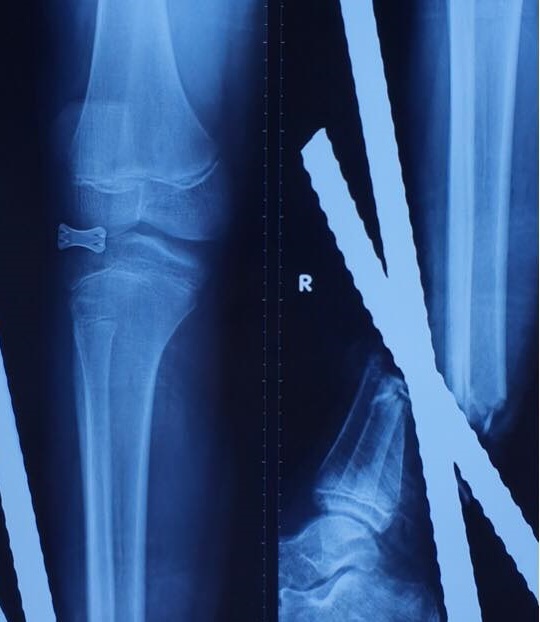

Ảnh chụp X-quang những cây sắt xuyên qua cổ chân và bàn chân. Ảnh:BSCC

Em N. nhập viện trong tình trạng 3 cây sắt đâm xuyên bàn chân và cổ chân phải. Theo lời kể của gia đình, bệnh nhi lái xe máy rồi tông vào xe ba gác, té vào đống sắt nên bị 3 cây đâm vào cổ chân và bàn chân. Lúc nhập viện, em N. được chẩn đoán gãy hở 1/3 dưới hai xương cẳng chân phải. Ê-kíp cấp cứu nhanh chóng đưa bé lên bàn mổ khẩn cấp, tiến hành cắt lọc, cố định xương bằng bất động ngoài, ghép động mạch chày trước, sau rồi nối cả dây thần kinh và gân.